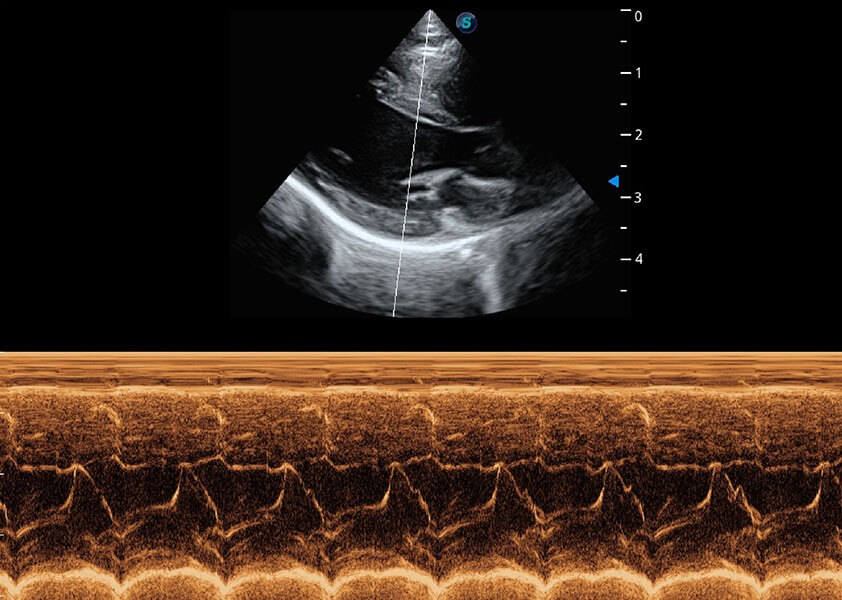

• AMM 解剖M型

通过360度任意调节3条M型取样线,在同一心动周期上观察心脏不同位置的运动曲线,得到准确的心功能测量数据,有效评估心肌运动及左心室功能。

(猫)二尖瓣M型